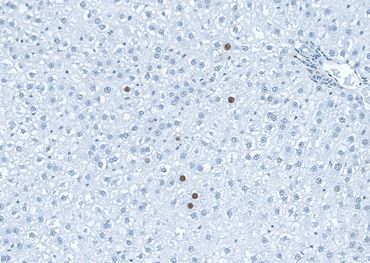

Kupffer cells in mouse liver (HIS36 IHC, frozen section). x80